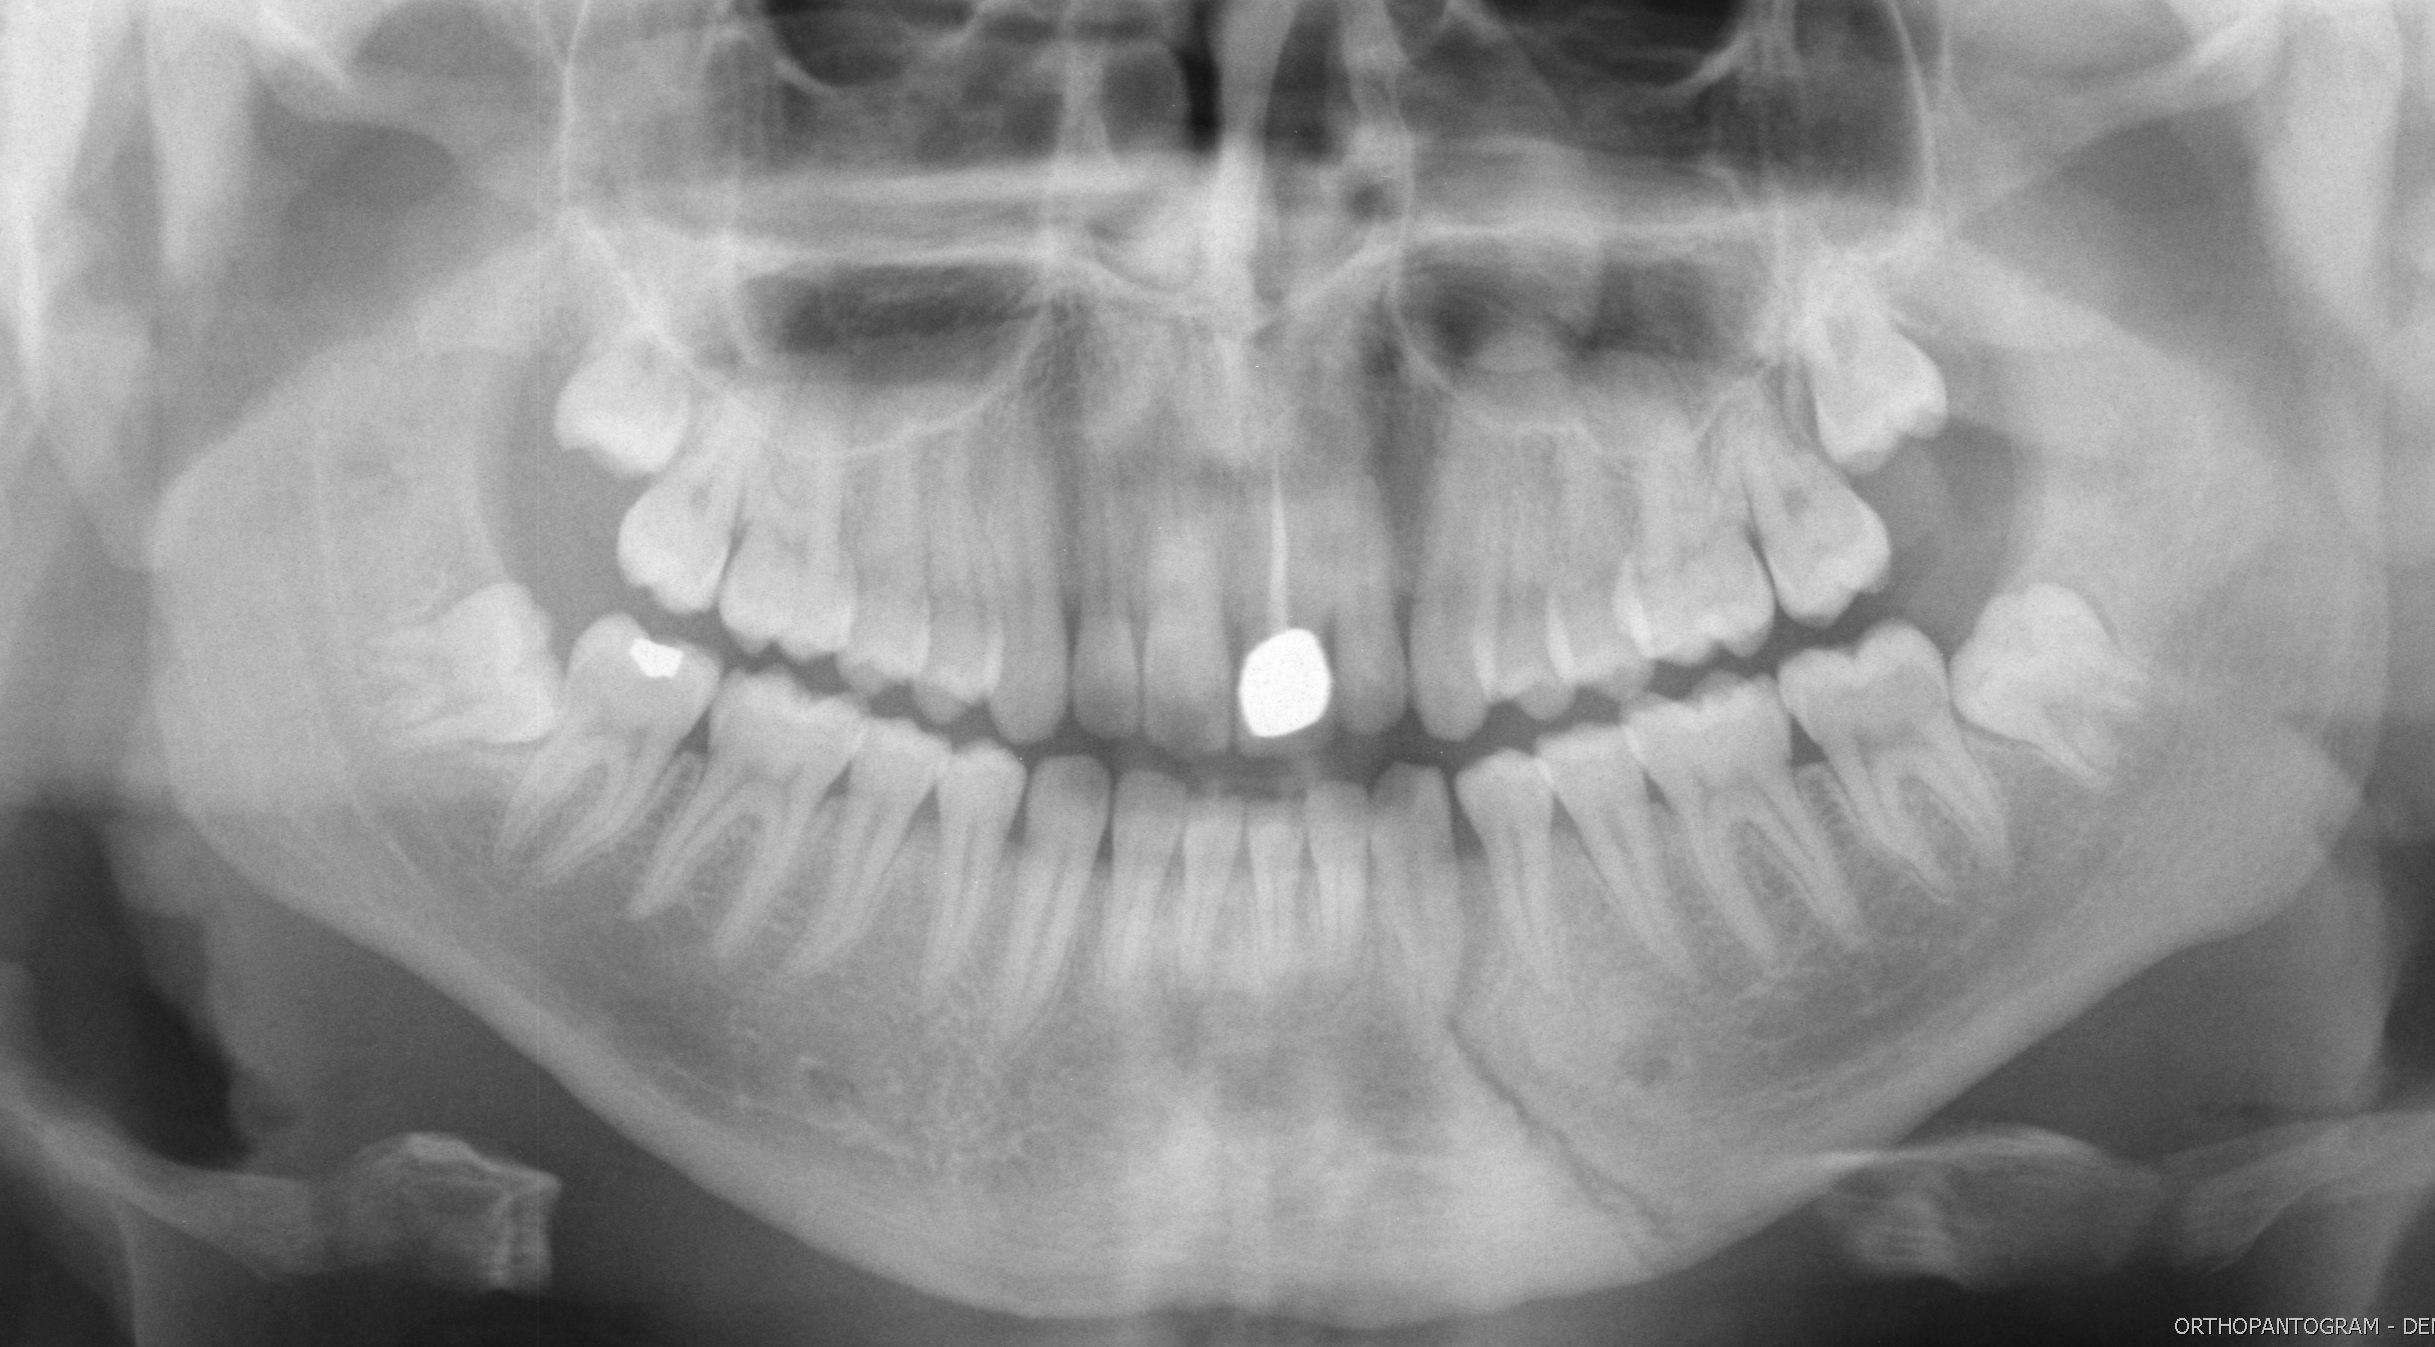

Ian Bickle, Radiopaedia.org. From the case rID: 50325

Radiographie panoramique dentaire puis hospitalisation dans le service de chirurgie maxillo-faciale pour une prise en charge au bloc opératoire.